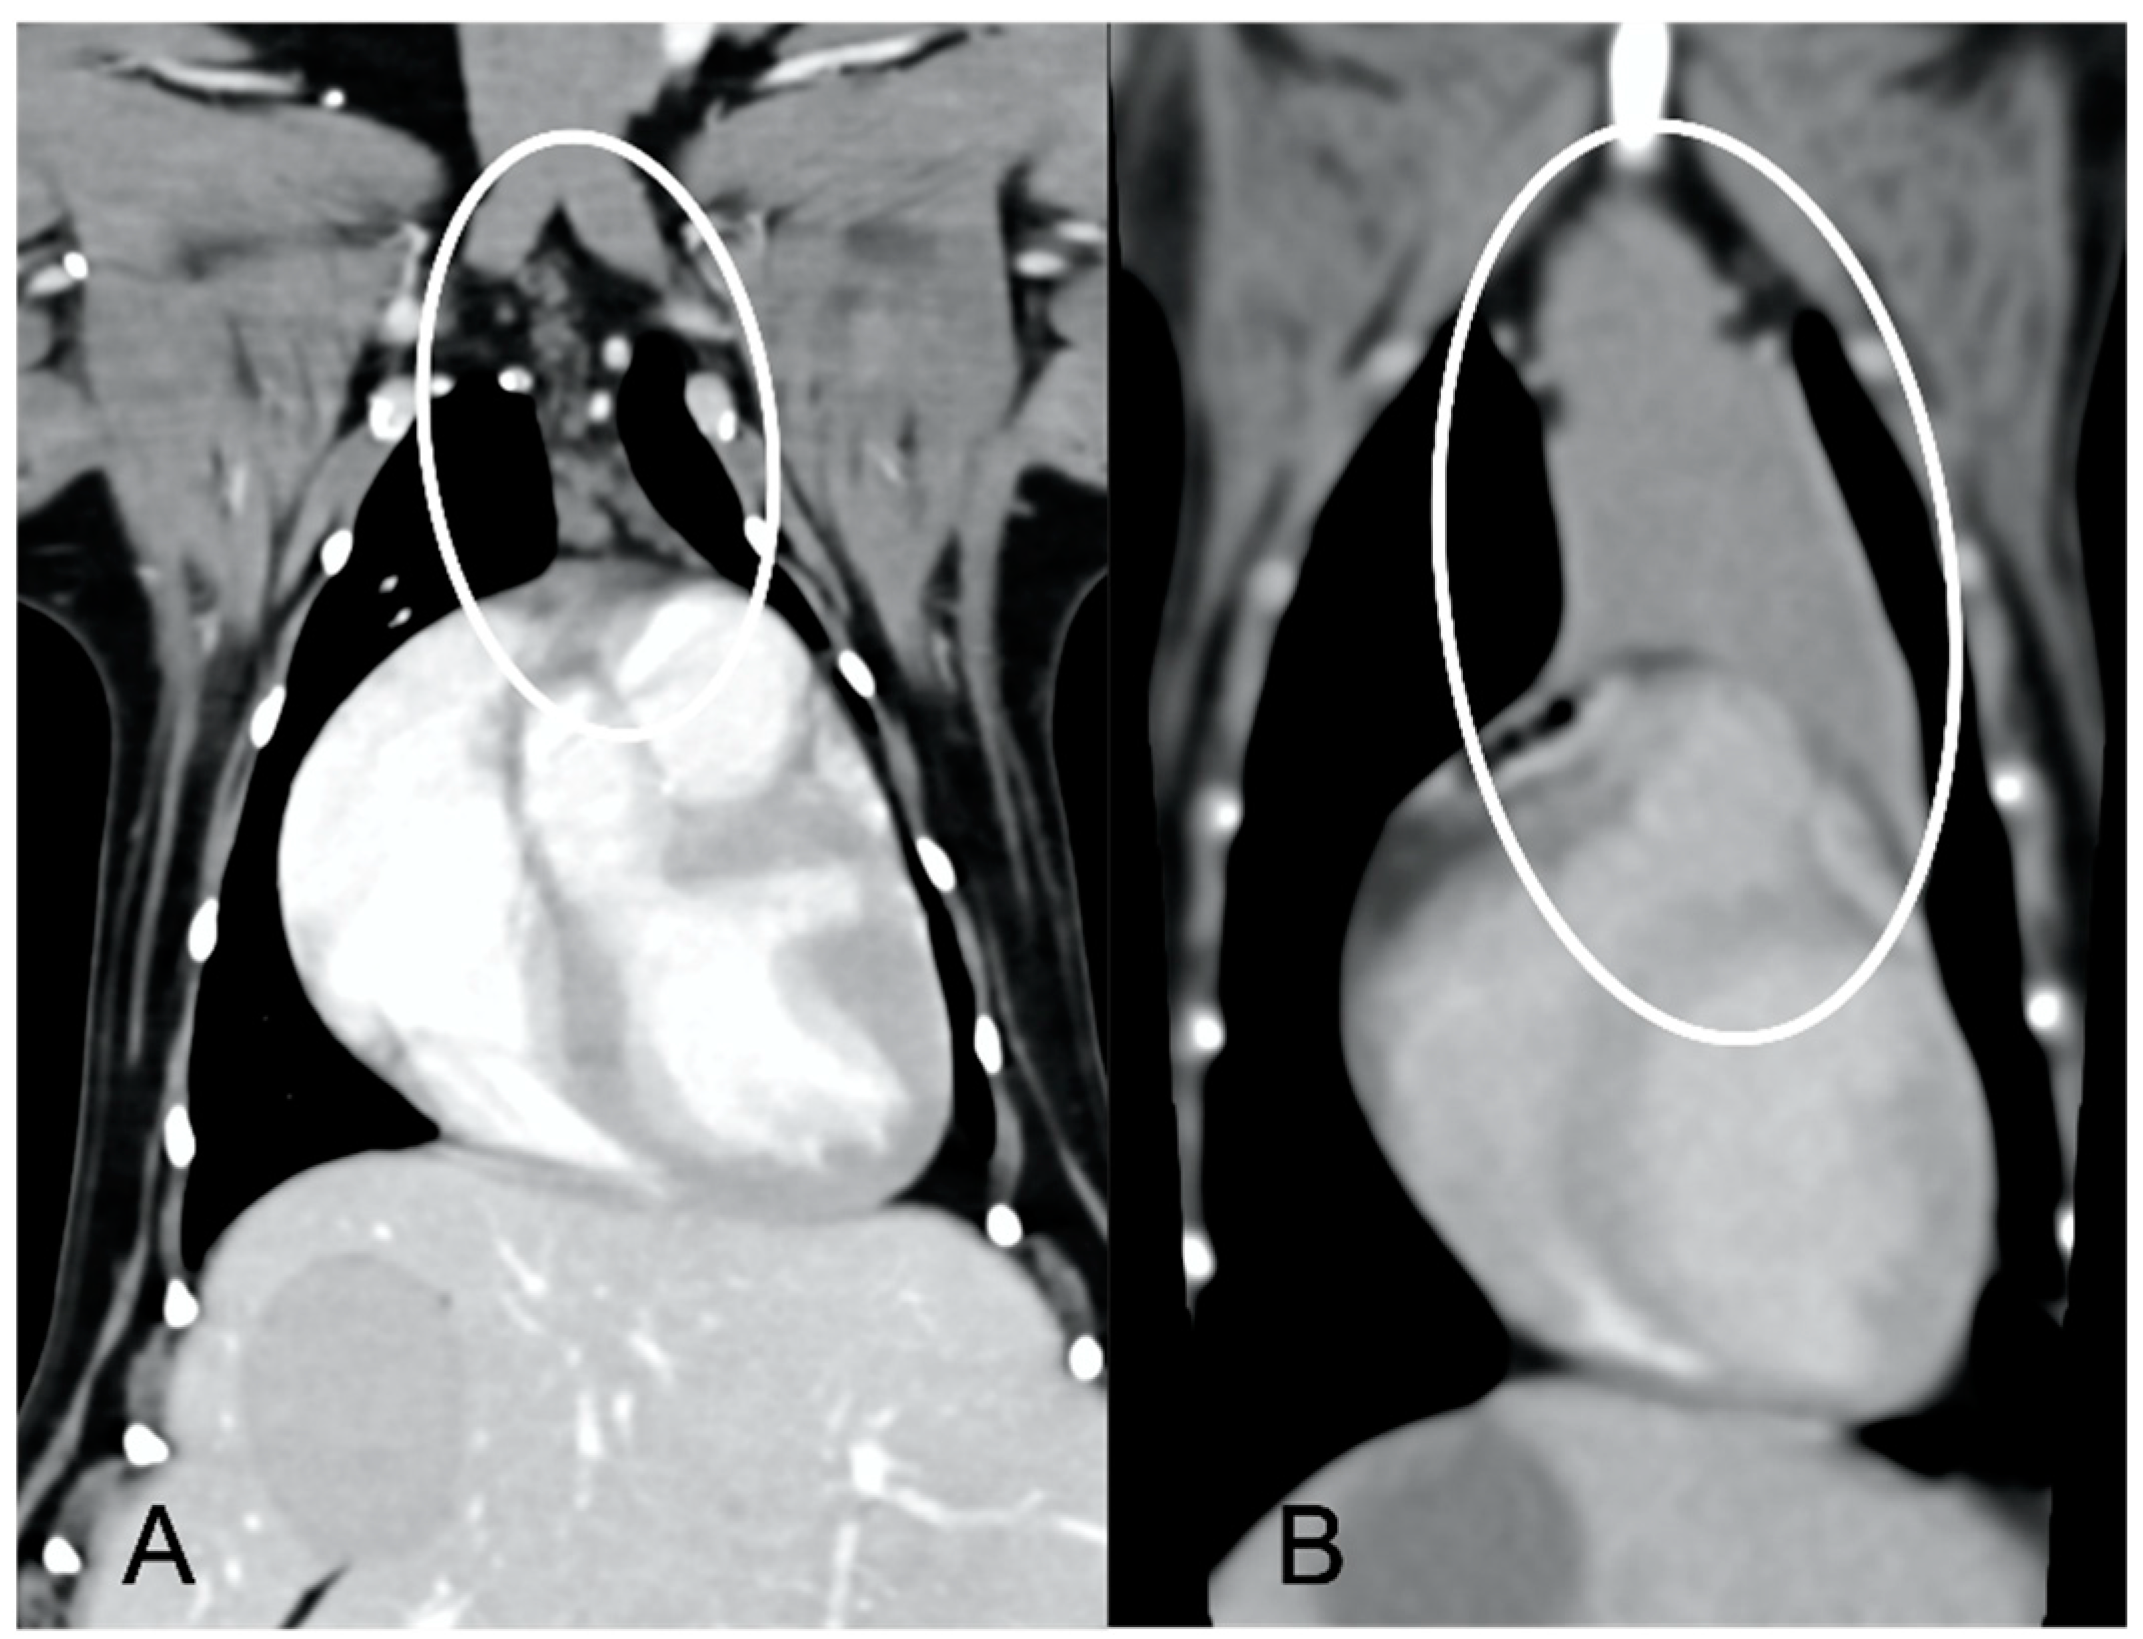

The overall appearance was lobulated in all of the adult dogs and homogeneous in all of the juvenile dogs (Figure 1 and Figure 3). The thymus was left-sided in all of the adult dogs, while it was located in the midline in a few juvenile dogs; one presented a thymus on the right side due to situs inversus (Figure 4). The maximum dimension of the thymus in the adult dogs group was always the length, while in some juvenile dogs, the maximum diameter was the width (Figure 2). The dimensions of the thymus were variable between different patients, with several breeds included and large differences in body weight between the dogs. For this reason, a ratio between the maximum diameter of the thymus (measured in cm) and the body weight (measured in kg) was calculated for each dog. The median ratio in the adult dogs group was 0.2 (minimum: 0.06; maximum: 0.4), while in juvenile dogs, it was 0.4 (minimum: 0.1; maximum: 1.4). The dogs with the higher ratio (>1) were in the juvenile group and they presented with spinal a cyst and enteritis and were 6 and 7 months old, respectively. The dogs with the lower ratio (<0.1) were in the adult group and they presented with muscular hemangiosarcoma (one dog) and synovial cell sarcoma (two dogs) and were 2, 6, and 8 years old, respectively.

The thymus was less attenuating in adult dogs compared to young dogs, with a median of the mean pre- and post-contrast attenuation values lower in adult dogs compared to juvenile dogs (Table 1). In 5/11 (45%) adult dogs, the minimum pre-contrast attenuation values were negative values (from −22 to −2 HU), due to the presence of multiple, hypoattenuating, thick septi within the thymic parenchyma (Figure 5).

Several CT features of thymic neoplasia have been described in dogs. Thymomas have been described as large, space-occupying masses arising from the cranial mediastinum, frequently heterogeneous or with a cystic appearance, mainly left-sided but being more centrally located with increasing size [6]. Vascular invasions have been reported, especially in larger masses [6]. Cranial mediastinal lymphomas have been described as more homogeneous masses compared to thymic epithelial neoplasms, more likely to envelop the cranial vena cava [7]. The CT characteristics of thymic neoplasia reported in these previous studies, such as large masses, heterogeneous, enveloping or invading the adjacent vasculature [6,7], were significantly different from the findings of the current study, in which the thymus was in fact considered non-neoplastic. The CT appearance of thymic hyperplasia in humans can be variable, but some features, such as bipyramidal morphology and the presence of gross intercalated fat (also described as ‘marbling’), are considered pathognomonic [20]. This appearance of ‘marbling’, with the presence of several hypoattenuating septations throughout the thymic parenchyma, was present in all of the adult dogs included in the current study, suggesting that these dogs may have presented with thymic hyperplasia at the time of CT examination.

Figure 5. Appearance of the thymus (circled) in an adult dog. Post-contrast transverse CT image (A) and dorsal reconstruction (B). Note the presence of multiple hypoattenuating septi within the parenchyma, giving the thymus a lobulated appearance and overall low attenuation.